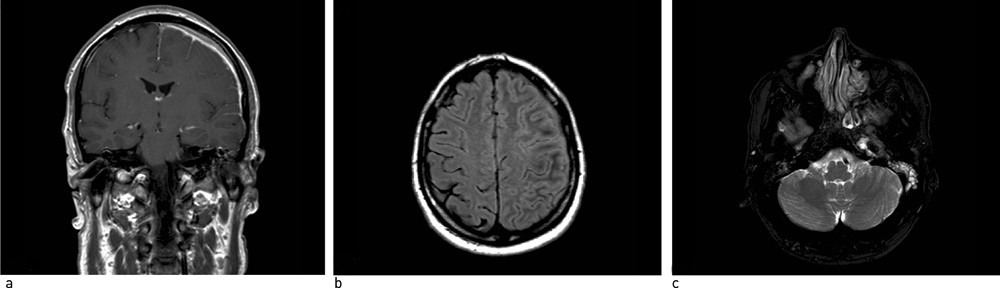

Etter hjemreise til Norge, tre uker etter symptomdebut utviklet pasienten tåkesyn på høyre øye og ble innlagt ved Universitetssykehuset Nord-Norge. Ved innkomst forelå det lett redusert allmenntilstand. Pasienten hadde betydelig redusert syn på høyre øye, øresus i venstre øre og lett dysartri. Omfattende blodprøvescreening viste senkning på 74 mm/h (2 – 12 mm/h), CRP på 83 mg/l (< 5 mg/l) og lett forhøyet c-ANCA (S-Anti-PR3) på 12 U/ml (negativ: 0 – 10 U/ml, positiv: 11 – 530 U/ml), men ellers normale funn. Ved spinalvæskeanalyse fant man lett pleocytose med hvite blodceller på 29 · 10⁶/l (< 5 · 10⁶/l) og totalprotein på 686 mg/l (< 500 mg/l). Åpningstrykket ved lumbalpunksjon var normalt. Øyelege konkluderte med optikusinfarkt på høyre øye. Øre-nese-hals-legen fant crustedanning i venstre nesekavitet, og det ble mistenkt lekkasje av cerebrospinalvæske fra venstre øre. Infeksiøst agens ble ikke påvist i noen av kroppsvæskene (blod, cerebrospinalvæske, øresekret, nasopharynx og urin). MR caput viste væskebrem med hevelse og kontrastopptak i meningene over venstre hemisfære samt væske i område av mastoid på venstre side (fig 1a–c). Dette ble tolket som sannsynlig meningeal effusjon. Det ble konkludert med bakteriell meningitt, og pasienten ble satt på antibiotika.

Pasienten hadde også klaget over nummenhet tilsvarende ophthalmicusgrenen fra nervi trigemini over affiserte øye. Hodepinen var nå mest lokalisert til høyre tinningregion opp mot pannen. Ny MR caput og regranskning av tidligere MR caput viste retrospektivt væske og bløtdelsoppfylning rundt venstre arteria carotis interna og vena jugularis under skallebasis (fig 1c). Tilstanden ble oppfattet som Wegeners granulomatose, med svakt positiv c-ANCA, slimhinnefortykkelse i bihuler, små nodulære fortetninger i lunger, ekstern oftalmoplegi med affeksjon av flere øyemuskler og nummenhet i panne – selv om ingen biopsifunn bekreftet diagnosen. Pasienten ble overflyttet til revmatologisk avdeling. På grunn av sykdommens alvorlighetsgrad ble han behandlet med intravenøs cyklofosfamid i seks måneder, med planlagt overgang til metotreksat som vedlikeholdsbehandling. Ved evaluering etter endt cyklofosfamidbehandling ble det imidlertid ved ny MR caput påvist økende fortykkelse av meningene, og pasienten ble gitt rituximab. Han har hatt god respons på denne behandlingen. Det er til nå gitt tre behandlingsrunder. Sykdommen er i remisjon, pasienten er symptomfri og tilbake i full jobb.

Nevroradiologisk undersøkelse spiller en sentral rolle i evalueringen av sykdommen. Imidlertid kan det ta to år før det tilkommer signifikante bildediagnostiske funn (19). CT-bilder avslører hyperintense durale lesjoner med homogen kontrastladning, men i enkelte tilfeller, for eksempel ved lite uttalt dural fortykkelse, påvises det ikke unormale funn (18). MR-undersøkelse er den beste metoden til å identifisere lesjonene og utelukke andre sykdomsprosesser. MR-funn er karakteristiske og viser forskjellige grader av lesjonens inflammatoriske mønster (5, 8). T1-vektede bilder viser isodens eller hypodens fortykket dura (6, 8, 9, 13) med intens forsterkning etter injeksjon av paramagnetisk kontrastmiddel, grunnet inflammatorisk reaksjon i pakymeningene. Dura mater opptrer hypointenst på T2-vektede bilder, i enkelte tilfeller omgitt av en hyperintens rand av lesjonen (8, 9, 13, 19). Det sentrale hypodense området er relatert til en fibrøs prosess, mens den perifere hyperintensiteten skyldes aktiv inflammatorisk reaksjon (9, 13). Bruk av gadolinium er viktig for å bedømme den meningeale ladningen, som kan brukes til å skille mellom pakymeningitt og leptomeningitt. MR-funn kan også gi en indikasjon på det kliniske forløpet. Diffus og homogen fortykkelse av dura og godt definerte T2-vektede randsoner er assosiert med kort klinisk forløp og god prognose. Hypodens hypertrofisk hjernehinne på T2-vektede serier, uten hyperdens rand og med dishomogen kontrastladning er forbundet med kroniske tilstander og ugunstig prognose (8).